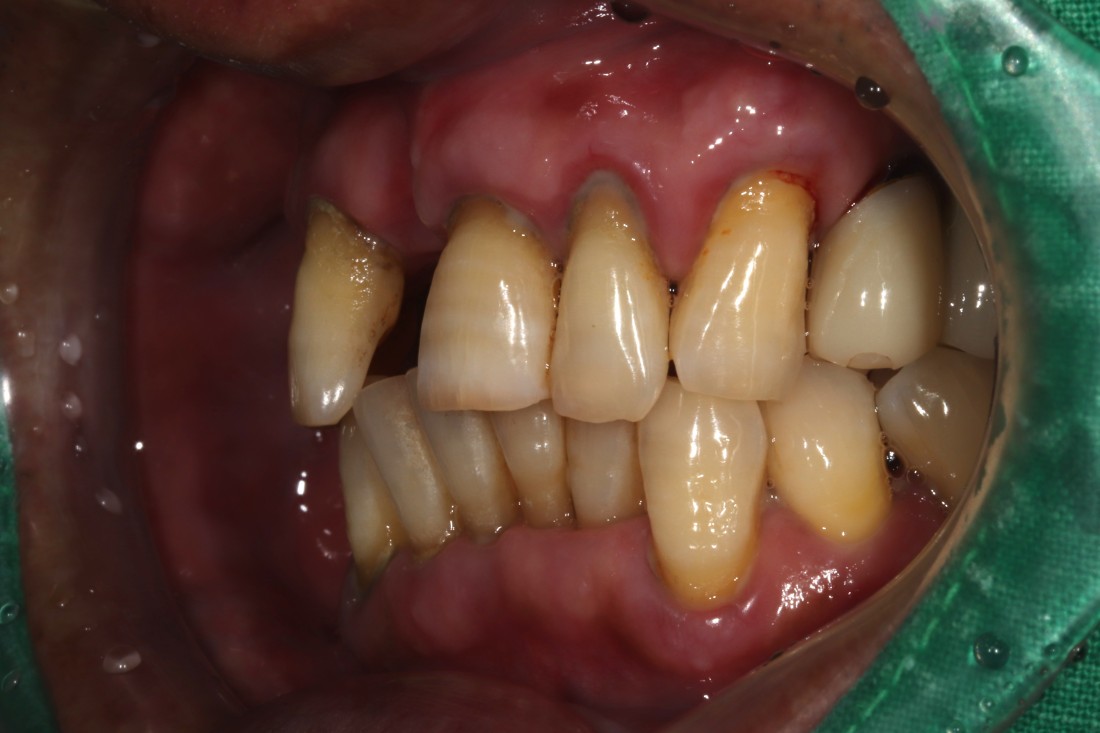

신경쓰이는 앞니 임플란트를

예쁘게 완성하는

광주 앞니임플란트 치과에서

광주 앞니임플란트가 필요할 때

무엇보다도 주변 치아와

잘 어울리고, 잘 씹어지는지가

앞니임플란트 성공의 포인트인데요.